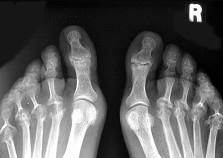

女,52岁,足跟痛,手指运动僵硬,请结合影像图像,选择最可能的诊断 ( )A、骨折B、类风湿关节炎C、骨脓肿D、骨囊肿E、骨质疏松

问题 女,52岁,足跟痛,手指运动僵硬,请结合影像图像,选择最可能的诊断 ( )

选项 A、骨折 B、类风湿关节炎 C、骨脓肿 D、骨囊肿 E、骨质疏松

答案 B